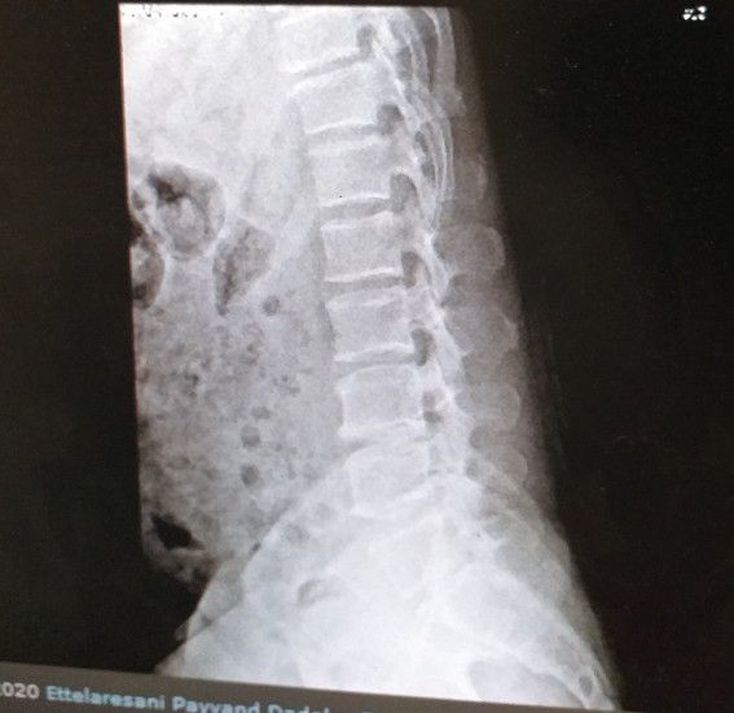

What is your diagnosis?

T11 compression fracture.

Really full of feces.

No the pathology in lumbar vertebrae?

But T not c 😅